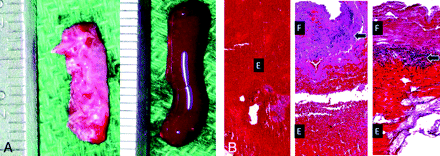

A, Macroscopic view of 2 different experimental clots. A novel experimental clot (fibrin-rich clot) (left) is prepared by manually excising the fibrin-rich layer of swine clot, which is created by natural sedimentation. Fibrin-rich clot shows more solid and elastic mechanical properties than conventional thrombin-induced experimental clot (erythrocyte-rich clot) (right). B, Microscopic view of the experimental clots versus thromboembolus recovered from a patient with acute stoke (H&E, original magnification ×40). A microscopic view of an erythrocyte-rich clot (left) demonstrates a thrombus composed predominantly of erythrocytes with interspersed fibrin and barium sulfate deposits. A thromboembolus recovered from a patient with stroke (center) shows distinct layers of fibrin, nucleated cells, and erythrocytes. A fibrin-rich clot (right) produces a layered pattern of fibrin, nucleated cells, and erythrocytes similar to that seen in the clot recovered from the patient with stroke (center). F indicates fibrin component; Arrows, the cellular component; E, the erythrocyte component.

Several samples of each clot type (fibrin- and erythrocyte-rich) were randomly selected and microscopically examined to evaluate their histologic characteristics (Fig 1B). The erythrocyte-rich samples were homogeneous in composition (composed almost exclusively of red blood cells) (Fig 1B, left). The fibrin-rich samples were complex in nature with well-defined fibrin-, cellular-, and erythrocyte-rich layers, respectively (Fig 1B, right).